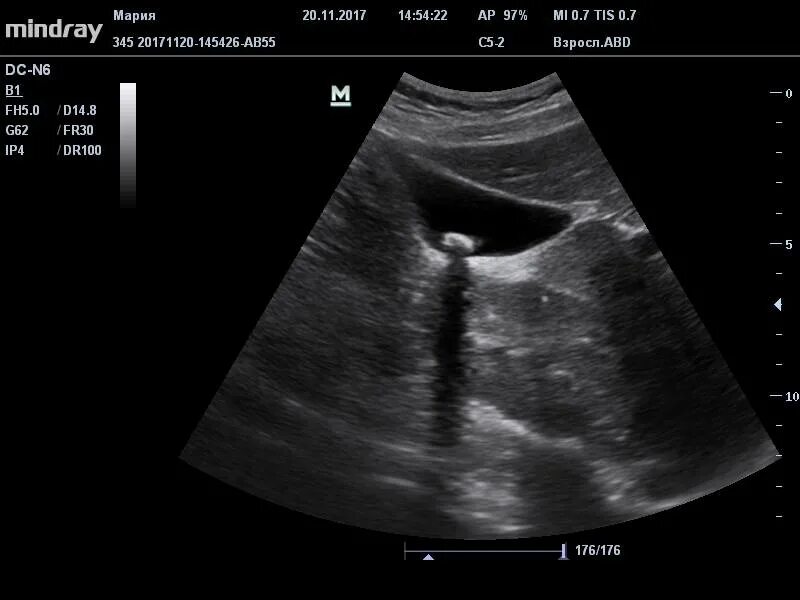

Как избавиться от полипов в желчном пузыре